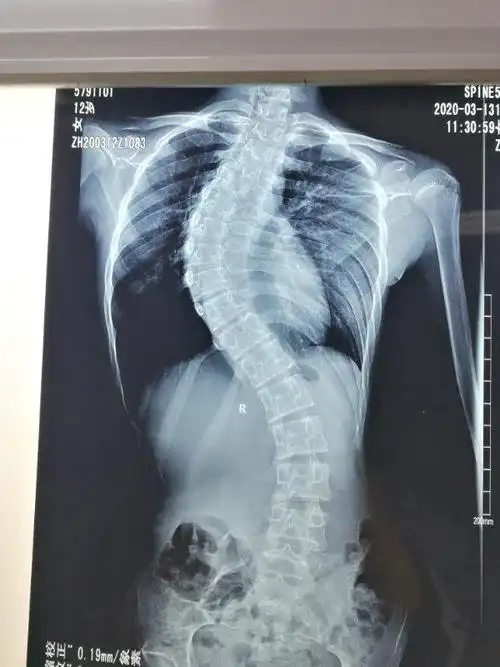

孩子肩膀一高一低,竟然不是脊柱侧弯,还有更严重的问题!

两边比较着看会更清楚,右边"方肩畸形",脱位明征, 左边肩部明显的圆顿

10岁时因为被家长发现双肩不等高,驼背,曾到医院就诊,当时虽然脊柱侧